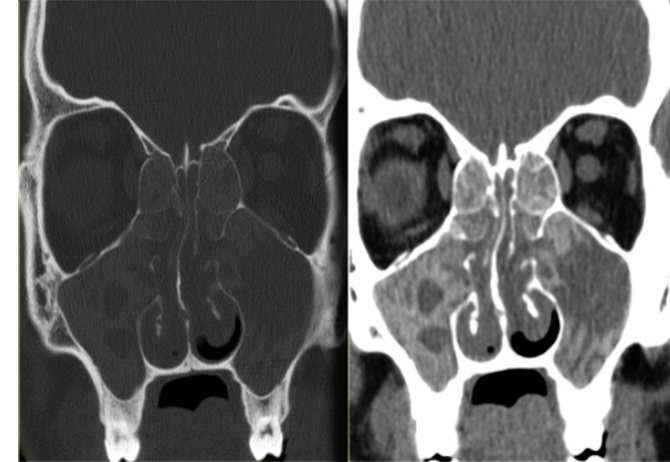

Fungal Sinusitis

- Question:

- Answer:

- A- What is the diagnosis?

- Fungal sinusitis

- B- What is the surgical treatment?

- Endoscopic sinus surgery

Chronic Rhinosinusitis

involved maxillary, ethmoid

heterogenous color, differences is fungal

management is conservative; nasal spray, irrigation - no antifungals